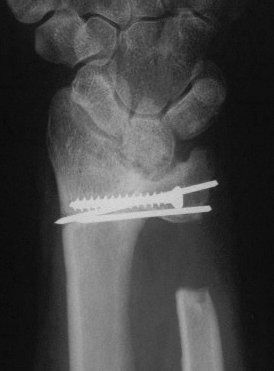

Case 3. Adult bilateral congenital Madelung's deformity with pain and extensor tendinitis, treated with the Sauve Kapandji (Lauenstein) procedure: segmental distal ulnar ostectomy and distal radioulnar joint fusion.

Right side, postop.